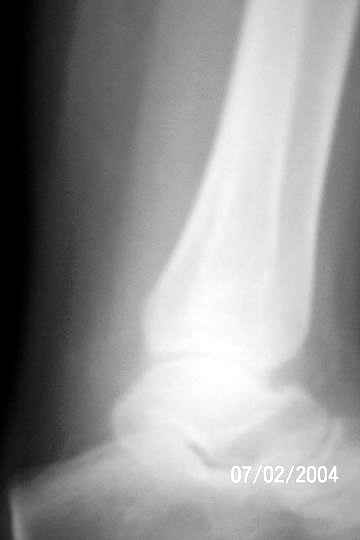

I am attaching an x-ray of 36 - years- old female patient had a cystic lesion with left fibula.

1 yrs back-curettage and bone-grafting elsewhere, for cystic lesion.

Biopsy report: Giant cell tumor – Grade 2